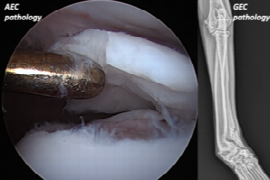

Following graduation from the University of Melbourne (2005) Ricky worked in general practice for 18 months prior to completion of a rotating internship at the University of Cambridge, surgical internship at the Veterinary Specialist Centre and surgical residency at the Small Animal Specialist Hospital in Sydney (2010-2013). Ricky remained at SASH until 2017 before joining the Southpaws Speciality Surgery for Animals team in Melbourne (current practice).

Ricky is a Fellow of the Australian New Zealand College of Veterinary Scientist in Small Animal Surgery. He has published and presented around the world with a strong and active interest in clinical and biomechanical research relating to the canine hip, stifle and spine, the focus of his current and previous research projects. He is a past recipient of the prestigious VOS Wade O Brinker Orthopaedic Resident Research Award (presented WVOC, Colorado 2014) and previous examiner for the ANZCVS small animal surgical chapter. He thoroughly enjoys all aspects of teaching, having taught at numerous workshops and conferences nationally and internationally while mentoring many residents and interns over the years.

Ricky’s primary surgical interests lie in orthopaedics and include arthroscopy, partial and total joint replacement, minimally invasive fracture repair and neurosurgery.